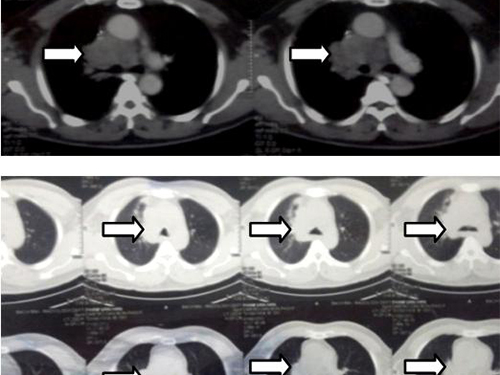

So sánh hình ảnh chụp CT ngực trước và sau điều trị

Hình 4: Chụp cắt lớp lồng ngực sau điều trị

Kết quả: Cho thấy bệnh nhân sau 6 tuần điều trị đáp ứng tốt, u tan gần hoàn toàn, không phải thở oxy, đi lại sinh hoạt được. Hiện tại bệnh nhân ổn định, sau phác đò hóa chất Navalbine bệnh nhân được chuyển qua phác đồ hóa chất khác để có được đáp ứng triệt để hơn.